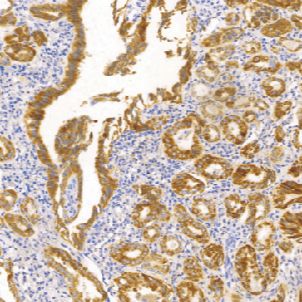

BRAFV600E 兔抗人BRAF V600E单克隆抗体

BRAF是人类重要的原癌基因之一。BRAF基因突变在多种癌症中被发现,包括非霍奇金淋巴瘤、结直肠癌、恶性黑色素瘤、甲状腺乳头状瘤、非小细胞肺癌和肺腺癌等。在不同的癌症中,BRAF突变率差异很大。目前多用于肿瘤和靶向药物的研究。

- 阳性部位:胞质

- 适用组织:石蜡切片

- 预处理:热修复

文献和实验Assaying for BRAF V600E in Tissue and Blood in Melanoma

The BrafV600E mutation has been detected in patients with metastatic melanoma, colon, thyroid, and other cancers. Studies suggested that tumors with this mutation are especially sensitive to BRAF inhibitors-hence the need to reliably

或可疑恶性患者的术后病理发现,仅20%~25%为甲状腺癌,而另75%~80%的患者则接受了不必要的甲状腺手术[3]。因此,如何正确处理这些FNAB无法确诊的病例,是目前面临的最大困难和挑战。 BRAF V600E是一个突出的PTC癌基因,占BRAF基因突变的80%,BRAF基因突变对PTC具有较好的特异性,BRAF突变阳性,几乎就可以确诊为PTC。因此,BRAF V600E对于乳头状甲状腺瘤来说是一种重要的诊断标记物,可以指导医师为细胞学诊断不能确诊的患者选择最佳的治疗方案。 表